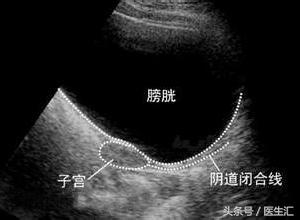

患者因为雌激素很低,子宫没有发育,B超不能准确判断是否为始基子宫。

始基子宫与幼稚子宫的区别:

始基子宫为双侧副中肾管融合后不久即停止发育,子宫极小,多数无宫腔或为实体肌性子宫,无子宫内膜,没有功能,再补充雌激素也长不大;幼稚子宫为双侧副中肾管融合形成子宫后发育停止所致,有子宫内膜。

子宫和人是一样的,人要靠吃饭长大,子宫要靠吃雌激素长大,患者为低雌激素性闭经,雌激素非常低,第二性征没有发育,B超子宫偏小,可能为幼稚子宫,是因为缺乏雌激素导致的,而低促性腺激素性闭经患者同时伴有子宫异常比较少见。

当补充雌激素后,患者第二性征发育,子宫也逐渐长大,当补充孕激素时,能撤退出血,表明这个子宫是有功能的,在当时未补充雌激素时为幼稚子宫;如果当补充雌激素后,患者第二性征发育,但子宫仍未长大,则为无功能的子宫,才称为始基子宫。